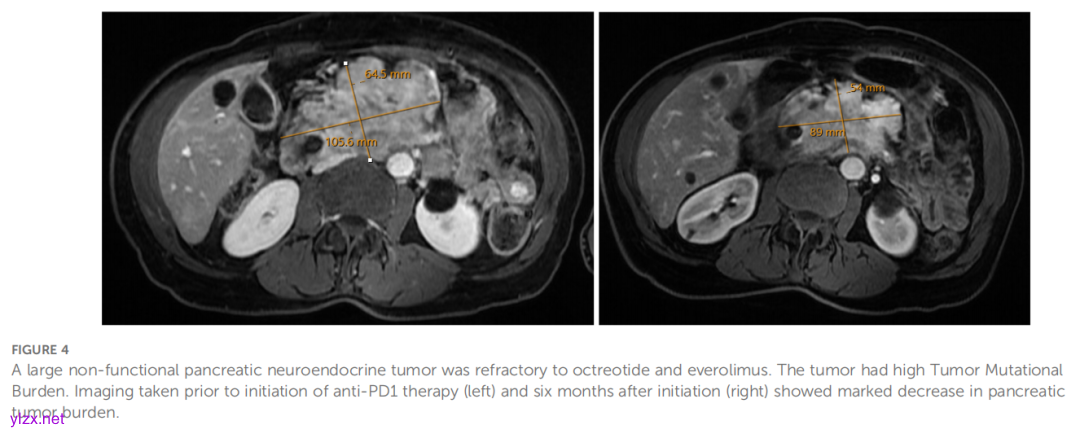

通过下一代测序进行分子检测,结果显示存在TP53和TSC2基因致病性突变,且肿瘤突变负荷(TMB)为 10.5 muts/Mb(排位为 89%)。值得注意的是,此时患者的肿瘤PD-L1表达为阴性。因疼痛问题,患者转诊至放射肿瘤科,并对原发肿瘤完成立体定向体部放疗(SBRT)。在继续奥曲肽与依维莫司治疗的基础上,基于TMB-H状态加用帕博利珠单抗。启动帕博利珠单抗治疗 6 个月后的再分期扫描显示,胰腺原发肿瘤及门静脉周围淋巴结肿大均较前缩小(图4)。治疗 9 个月时复查磁共振成像(MRI)显示肿瘤体积进一步减小。患者病程中曾并发中性粒细胞减少症、直肠结肠炎、产志贺毒素大肠杆菌感染及艰难梭菌感染。自启动帕博利珠单抗治疗至今已超过两年,患者仍维持疾病控制,唯一新增并发症为胆道梗阻需行外引流治疗。

▲图4 胰腺神经内分泌肿瘤对奥曲肽和依维莫司具有耐药性